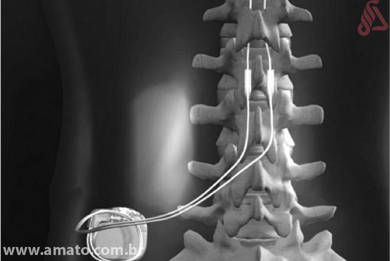

Neuroestimulador. Un neuroestimulador es una batería que produce un estímulo eléctrico, este estímulo es transmitido a la medula a través de un electrodo. Para colocar un neuroestimulador debemos de hacer una pequeña intervención que se realiza sin anestesia general que consite en situar el electrodo en la medula y la batería por debajo de la piel.

Existen estudios que demuestran que un neuroestimulador puede conseguir resultados satisfactorios en el 50-60% de los casos de cirugía fallida de columna, incluso el 15% de los pacientes pueden recuperar su vida laboral. No parece mucho, pero recuerda que los pacientes diagnosticados de síndrome post-laminectomia son personas multioperada con lumbalgia y ciáticas crónicas y serias limitaciones para realizar actividades cotidianas.

Antes de implantar un neuroestimulador hay que descartar otras causas de mal resultado de una cirugía de columna que puedan ser resueltas de una manera definitiva. Recuerda que una falta de fusión, una inestabilidad, o una recidiva de una hernia discal son causas de dolor que tienen una solución definitiva mediante cirugía.

Sin embargo en los casos de síndrome post-laminectomía el neuroestimulador es más eficaz para el control del dolor que una cirugía que incluso podría agravar los síntomas.